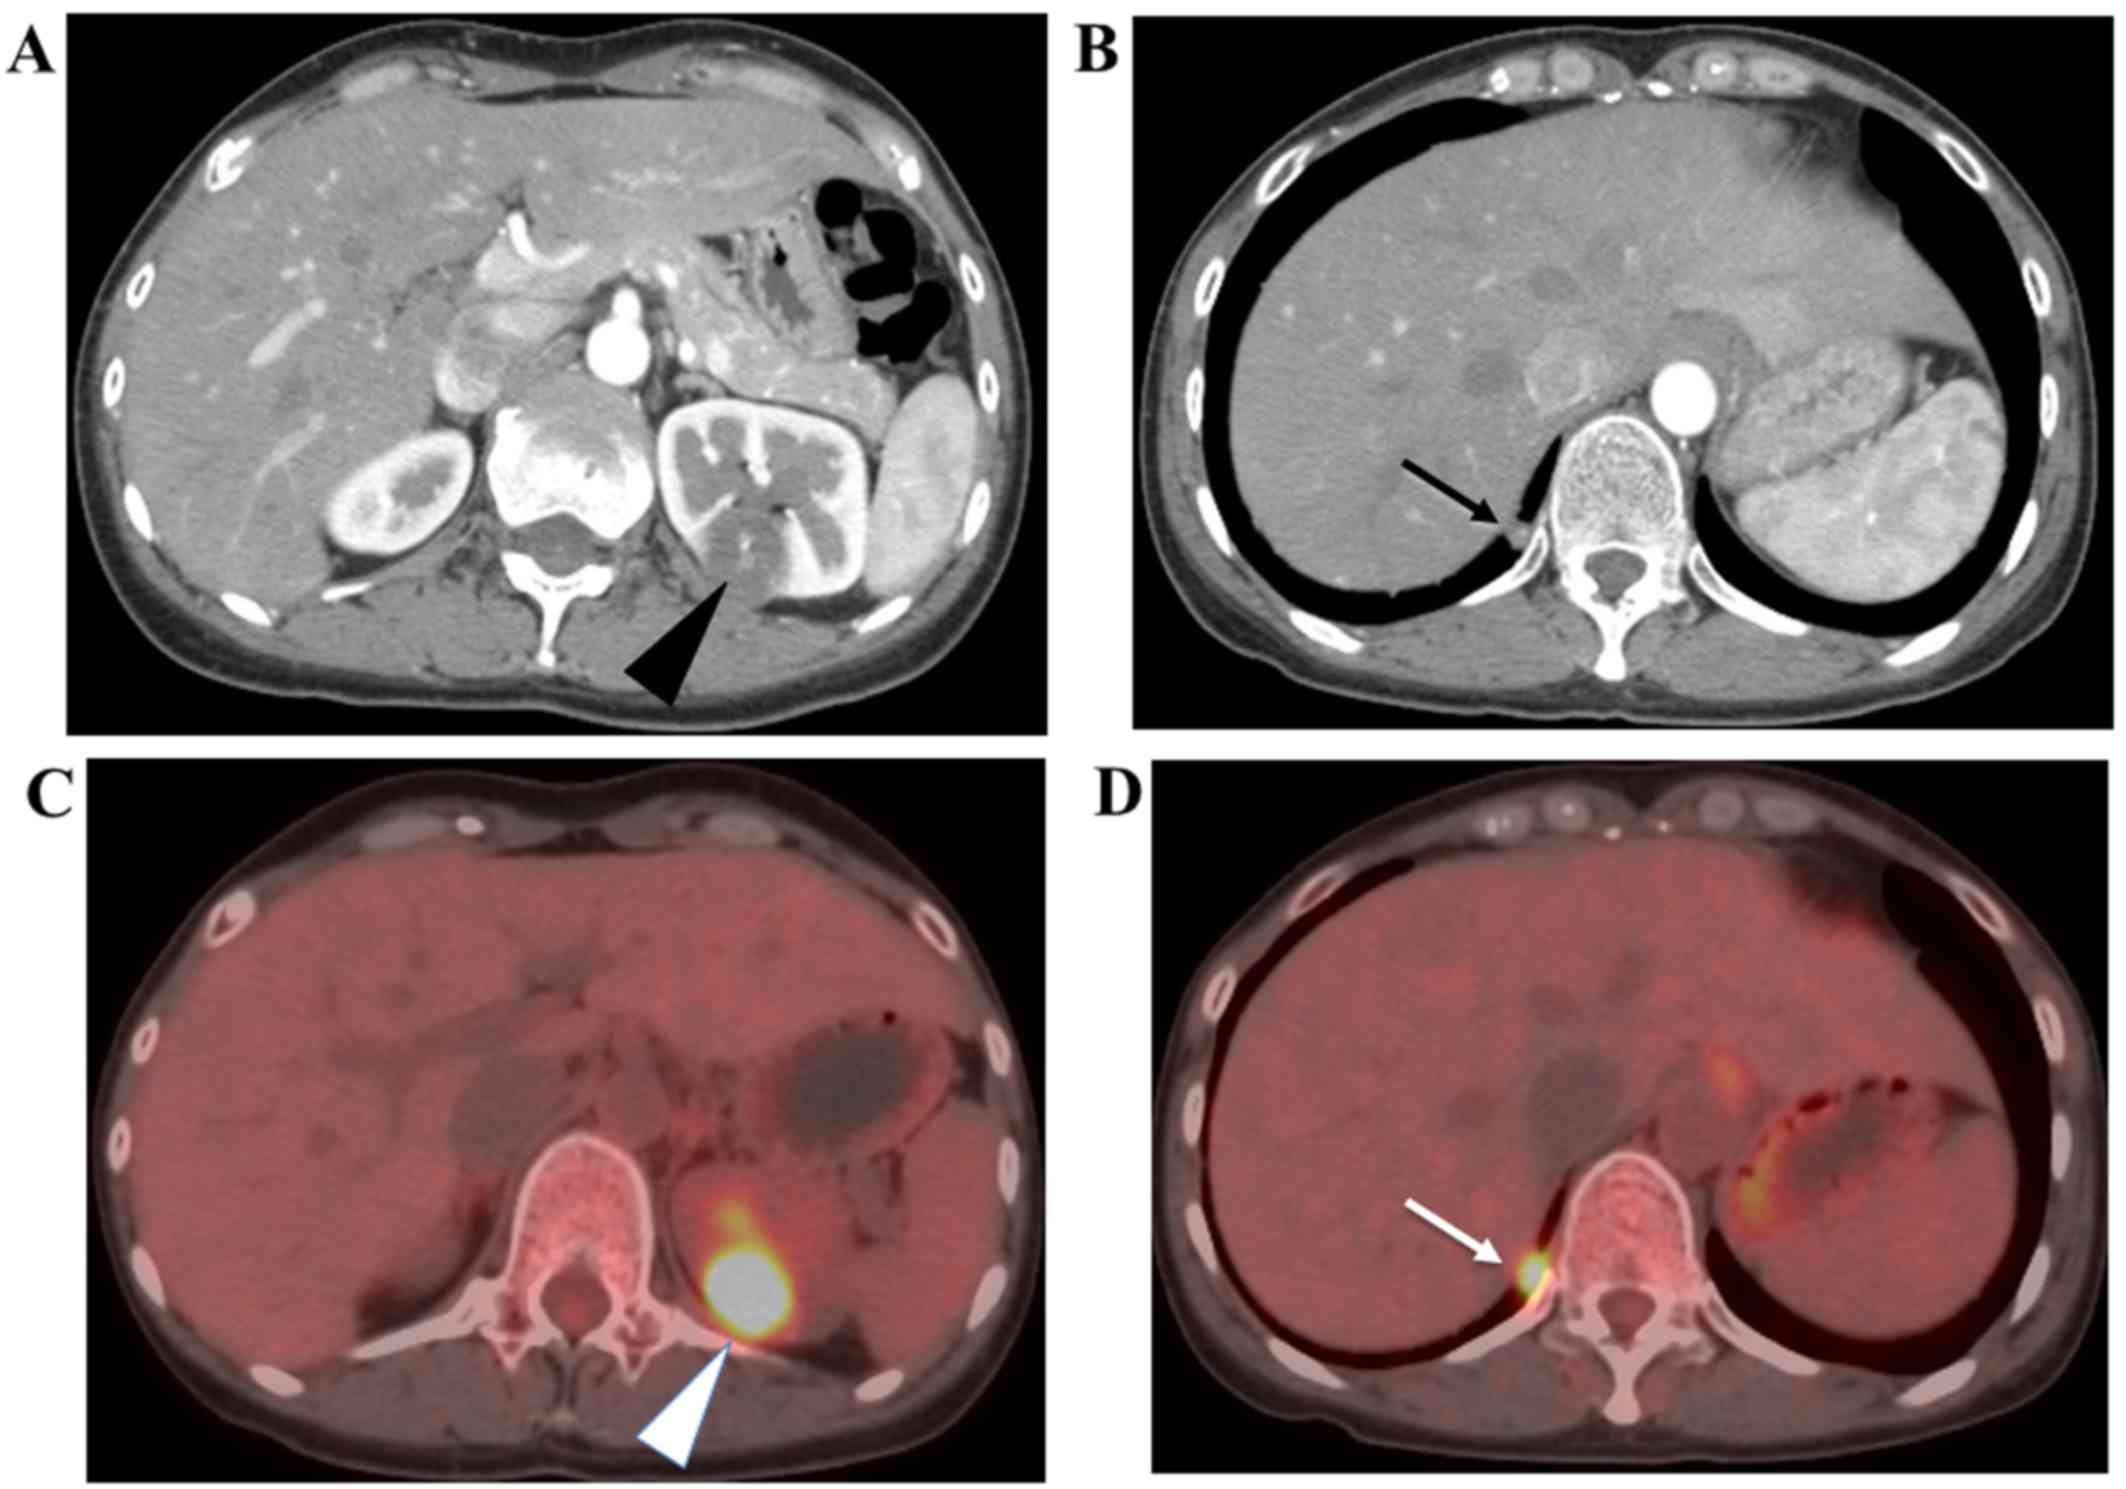

Five months after the second parturition, a 36-year-old woman visited a nearby hospital due to secondary amenorrhea with nausea after obtaining a positive result on a urinary pregnancy test. She had a past history of two normal vaginal deliveries of male babies 4.5 years and six months ago, respectively, and received artificial abortion one time. Although the serum level of human chorionic gonadotropin (hCG) was elevated at 51,800 mIU/ml, a gestational sac was not observed in the uterus or bilateral adnexa by ultrasonography. Computed tomography (CT) and magnetic resonance imaging (MRI) did not detect a gestational sac in the genital tract, but showed abnormal solitary tumor features in the left kidney and right lung (Fig. 1A). Positron emission tomography-computed tomography (PET-CT) confirmed that both tumor lesions showed a high uptake of 18F-FDG (Fig. 1B). Pathological examination by endometrial curettage was negative for an intrauterine conceptus. The ultrasonographic characterization of the renal lesion suggested renal cell carcinoma. Therefore, to determine whether it was metastatic trophoblastic disease or renal cell carcinoma, we biopsied the renal lesion with a fine needle technique (Fig. 2A), and obtained a final pathological diagnosis of choriocarcinoma (Fig. 2B and C). We chose a chemotherapeutic regimen comprising etoposide, methotrexate, actinomycin-D, cyclophosphamide and vincristine (EMA/CO chemotherapy) and performed 10 courses. The serum hCG level was successfully reduced to less than 1 mIU/ml. The enhanced CT confirmed the size reduction of both tumors with avascular changes. The uptake of 18F-FDG by PET-CT was also diminished. No sign of recurrence was observed during the 18-month follow-up period.

Figure 1.

Enhanced CT and PET-CT images. (A and B) Enhanced CT images. (A) A slightly enhanced tumor lesion of 3.5 cm in its longest diameter was observed in the posterior wall of the left kidney (arrowhead). No hemorrhagic lesion was detected in the tumor. (B) A solitary lesion was observed in the posterior pleural cavity of the right lung (arrow). (C and D) PET-CT images. High uptake of 18F-FDG was observed in both tumors in the kidney (arrowhead) and in the pleural cavity (arrow).